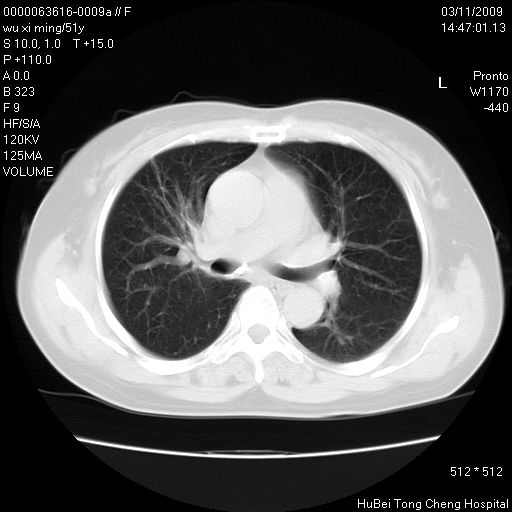

患者 女,51岁。因“胆囊炎,胆囊结石”,行常规术前胸部x线检查发现:右上肺结节病灶,建议行进一步检查。患者无咳嗽、咳痰及咯血等呼吸道症状,近期出现背部疼痛不适。

胸部ct轴位平扫(层厚10mm,螺距1.5,重建间隔10mm;部分层面:层厚3mm,螺距1.0,重建间隔3mm),图像如下:

1、周围型肺癌。(毛刺正、血管束集征,分叶。)

集束征,胸膜牽拉征,毛刺,淺分葉高度提示ca.

右肺周围型肺癌伴肺内转移及胸椎转移。已无手术机会。